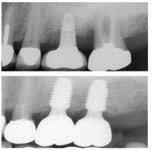

Christopher Chung, DMD

Smile Again Dental Group 818-776-9300

์์น์ง์ ๋ง์น๊ณ ๋์ ๊ฐ๊ธ ํ ๋ฒ ํ๋ฉด, ์

์์ด ํจ์ฌ ๊ฐ์ดํด์ง๊ณ ์์พํ ์ฃ . ์ฌ์ค ๊ฐ๊ธ์ ๊ทธ๋ฅ ์๋ฌด๊ฑฐ๋ ์จ๋ ๋ค ๋น์ทํ ๊ฒ ๊ฐ์ง๋ง, ์ฑ๋ถ๊ณผ ์ฉ๋

์ ๋ฐ๋ผ ๊ฝค ํฐ ์ฐจ์ด๊ฐ ์์ต๋๋ค. ์ด๋ค ๊ฐ๊ธ์ด ์น์ ๊ฑด๊ฐ์ ๋์์ด ๋๋ ์ง, ๋ ์ธ์ ์ด๋ป๊ฒ ์ฌ์ฉํ๋ ๊ฒ ์ข์์ง ์กฐ๊ธ ๋ ์์ธํ ์ ๋ฆฌํด๋ดค์ต๋ ๋ค.